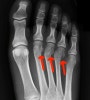

발의 AP view, lateral view, oblique X-ray 촬영을 실시합니다.

X-ray : 중족골 골절(Metatarsal head fracture)